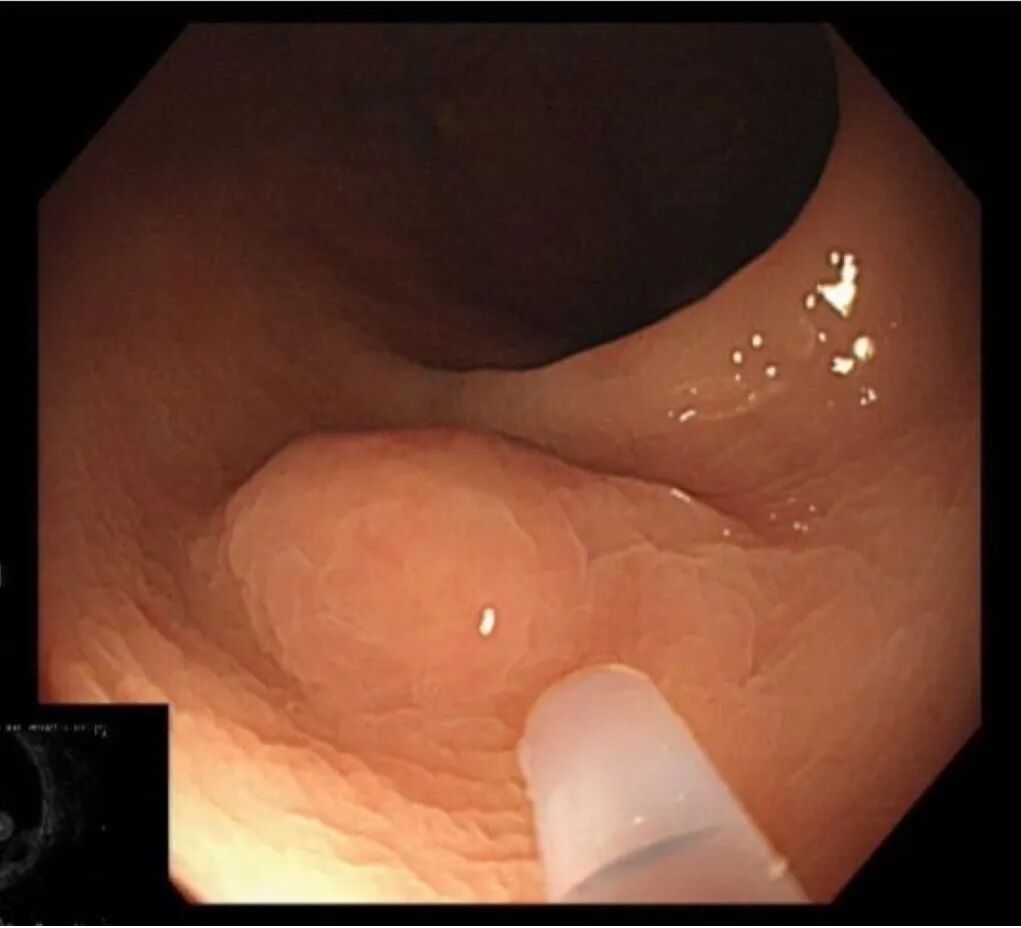

赵某某,男,61岁,因“腹部不适伴大便次数增多2月余”入院,完善肠镜检查:直肠见一直径1.2cm 黏膜下隆起。超声内镜:直肠粘膜肌层低回声隆起,考虑神经内分泌肿瘤。

神经内分泌肿瘤有远处转移可能,与患者家属详细沟通、解释病情,完成充分的术前评估及准备后,孙院长实施黏膜下肿瘤挖除术,成功将病灶切除;术后病理诊断“神经内分泌肿瘤”,患者康复出院。